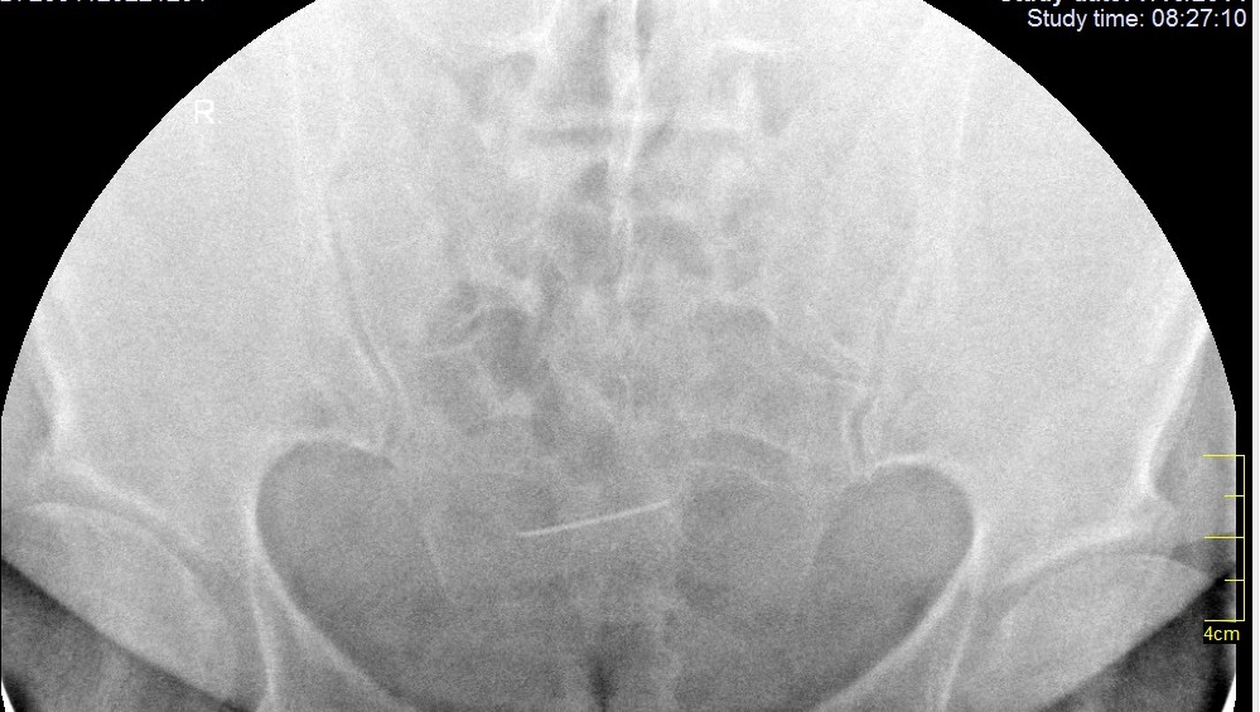

În răspunsul primit de la Colegiul Medicilor se precizează că – în timpul intervențiilor chirurgicale – nu se folosesc ace drepte, ci numai ace curbe.

„În timpul intervenţiilor noastre din sfera pelvină nu se folosesc ace drepte, ci numai ace curbe, nici nu am avut vreodată în spital ace drepte pentru sutură. În concluzie, este dificil de a face legătură cauzală între imaginea radiologică prezentată în copie xerox, simptomele declarate de sesizantă şi operaţia care a avut loc cu 23 de ani în urmă“, se menţiona atunci în răspunsul oferit de Colegiul Medicilor Iaşi.